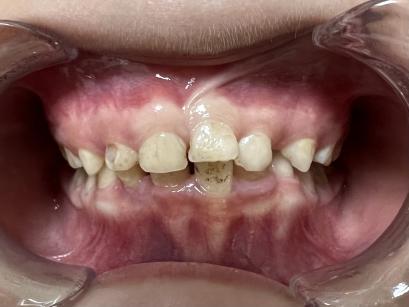

案例一:

治疗前